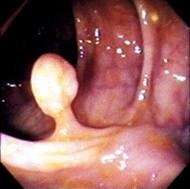

Aspect coloscopie du polyp

pediculaire du colon . |

hyperplasique a sessile du colon (A') , polyp pediculaire ( B') et adenocarcinoma du colon (

C') |